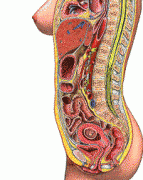

胎儿(相关胎儿专题知识分享)

胎儿专题是妈妈宝宝网胎儿精心为大家收集整理的,提供有关于胎儿的相关知识文章,是妈妈宝宝网以及众多网友分享的有关于胎儿相关经验和体会,以及其有关问题的提问和解答。